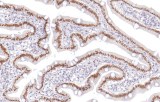

Primary antibodies for immunohistochemistry (IHC) with CE/IVD marking are essential reagents in diagnostic and research pathology, enabling the specific detection of target antigens in formalin-fixed paraffin-embedded (FFPE) tissue sections.

IHC using CE/IVD primary antibodies is a cornerstone in the characterization of gastrointestinal tumors. These antibodies assist pathologists in distinguishing epithelial from mesenchymal origins, determining tumor subtypes, and identifying primary sites in metastatic disease.

- In colorectal cancer, antibodies against cytokeratins (CK7, CK20) and transcription factors such as CDX2 facilitate accurate tumor classification and subtype differentiation.

- In gastric and esophageal adenocarcinomas, IHC highlights metaplastic and dysplastic changes, supporting early detection and prognostic evaluation.